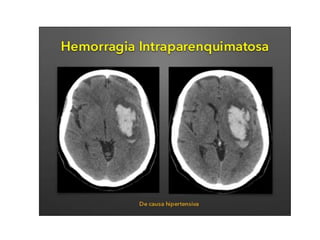

TAC

•medio diagnóstico de elección

para la determinación de la

hemorragia, su topografía,

extensión y apertura al líquido

cefalorraquídeo

•presencia de edema y

desplazamiento de estructuras, y

evaluar, evolutiva-mente, su

resolución o aparición de

complicaciones.